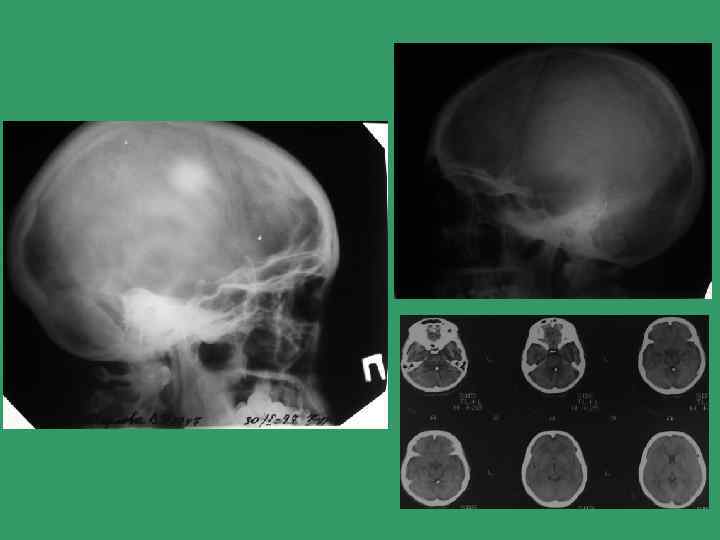

Алгоритм лучевого обследования при синдроме головной боли • Уровень I Норма Рентгенография черепа Внутричерепная гипертензия Внутричерепные обызвестления Рентгенография шейного отдела позвоночника Уровень II КТ, МРТ КТ

Внутричерепные обызвествления